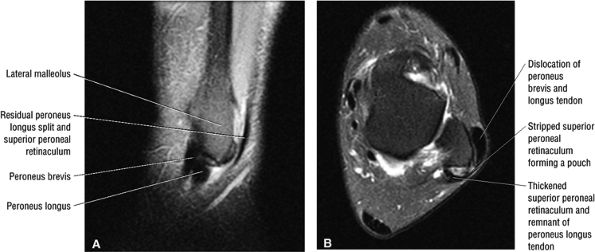

The peroneal retinaculum prevents the peroneal tendons from subluxing laterally over the lateral malleolus. Tears or stripping of the peroneal retinaculum from the lateral malleolus is inferred when subluxation or dislocation of the peroneal tendons is seen lateral to the lateral malleolus.